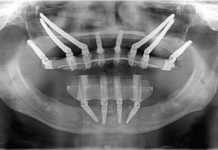

Framework in Metallo su Impianti (Video)

L’importanza di un buon risultato per un dispositivo protesico comincia dalla progettazione.

Visione, precisione, semplificazione, controllo, sono poche e alcuni benefici che gli strumenti digitali,...